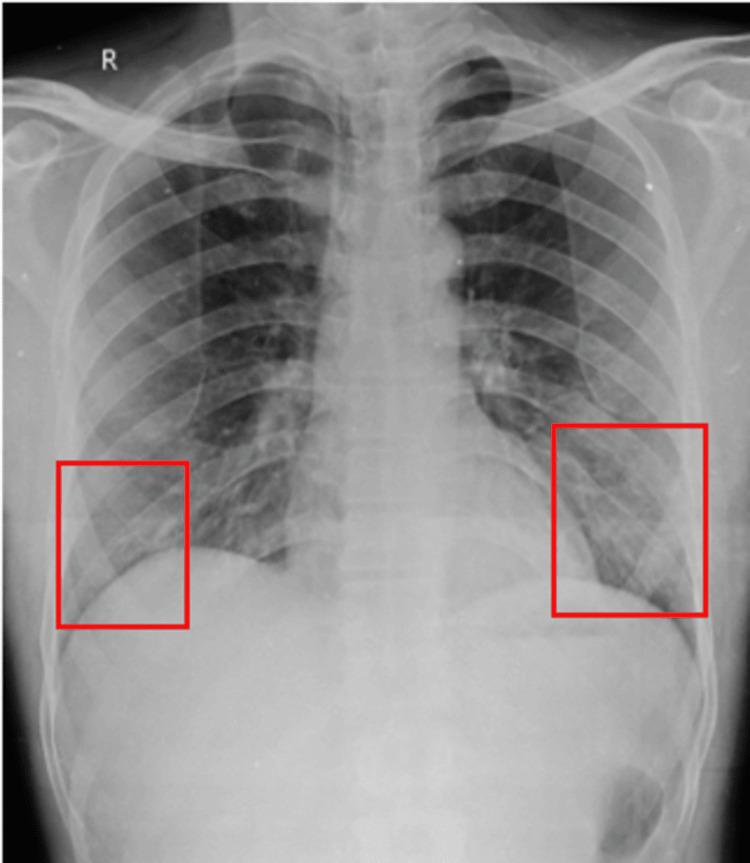

Organophosphate poisoning (OPP) remains a significant public health issue globally, particularly in middle- and low-income countries. This study aimed to assess the effectiveness of physiotherapy interventions in managing patients with OPP, focusing on reducing the severity of intermediate syndrome symptoms and associated complications such as respiratory muscle weakness and bilateral loculated pleural effusions. A 48-year-old male with a history of alcohol consumption was transferred to the medicine intensive care unit due to poison ingestion. The patient exhibited symptoms of respiratory distress and decreased consciousness, necessitating intubation and mechanical ventilation. Physiotherapy interventions included patient education, secretion mobilization, vital capacity improvement, secondary complication prevention, chest expansion exercises, dyspnea-relieving positions, and mobilization. The patient's progress was monitored using various scales, including the Functional Independence Measure Scale, ICU Mobility Scale, and Chelsea Critical Care Physical Assessment Tool. Significant improvements in functional independence, mobility, and psychological well-being were observed throughout the intervention period. This study highlights the importance of physiotherapy in the comprehensive management of OPP, emphasizing its role in mitigating respiratory complications and improving overall functional outcomes.

有机磷中毒(OPP)在全球范围内仍然是一个重大的公共卫生问题,尤其是在中低收入国家。本研究旨在评估物理治疗干预对OPP患者的管理效果,重点是减轻中间综合征症状的严重程度以及相关并发症,如呼吸肌无力和双侧包裹性胸腔积液。一名有饮酒史的48岁男性因中毒摄入被转入内科重症监护病房。患者出现呼吸窘迫和意识下降症状,需要插管和机械通气。物理治疗干预包括患者教育、分泌物清除、肺活量改善、继发性并发症预防、胸部扩张练习、缓解呼吸困难的体位和活动。使用各种量表监测患者的进展,包括功能独立性测量量表、ICU活动量表和切尔西重症监护物理评估工具。在整个干预期内,观察到功能独立性、活动能力和心理健康有显著改善。本研究强调了物理治疗在OPP综合管理中的重要性,强调了其在减轻呼吸并发症和改善整体功能结局方面的作用。